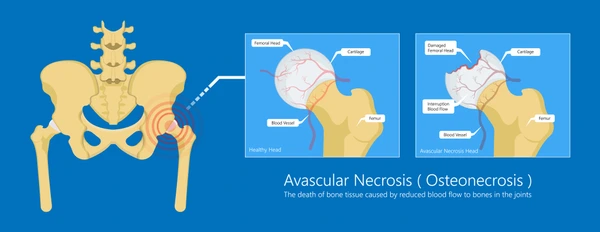

चिखली (Buldhana), ३० डिसेंबर २०२५: मलेशियात नोकरीनिमित्त वास्तव्य करणाऱ्या एका भारतीय व्यक्तीला गेल्या १८ वर्षांपासून कूल्ह्याच्या सांध्यातील असह्य वेदनांनी ग्रासले होते. डॉक्टरांनी त्यांना अव्हॅस्क्युलर नेक्रोसिस (AVN) असल्याचे सांगितले होते आणि शस्त्रक्रिया हाच एकमेव उपाय असल्याचे सांगितले. मात्र, आर्थिक अडचणी आणि उपचारांच्या खर्चामुळे त्यांनी वेदनांशी तडजोड करत आयुष्य जगणे पसंत केले. अखेर २०२५ मध्ये महाराष्ट्रातील चिखली येथील गंगाई हॉस्पिटलमध्ये आयुर्वेदिक उपचारांनी त्यांना अवघ्या ७ दिवसांत दिलासा मिळाला. हा अनुभव आयुर्वेदाच्या सामर्थ्याची एक प्रेरणादायी कथा आहे.

मलेशियात राहणाऱ्या या रुग्णाला १८ वर्षांपूर्वी कूल्ह्याच्या सांध्यात तीव्र वेदना सुरू झाल्या. अनेक नामांकित डॉक्टरांनी तपासणी केल्यानंतर AVN चे निदान झाले. “शस्त्रक्रिया व्यतिरिक्त दुसरा पर्याय नाही,” असे डॉक्टरांनी स्पष्ट केले. मात्र, घरची आर्थिक परिस्थिती साधारण असल्याने आणि शस्त्रक्रियेचा प्रचंड खर्च तसेच दीर्घकाळ उपचार परवडणारे नसल्याने रुग्णाने हा मार्ग टाळला. त्यावेळी AVN या आजाराबाबत फारशी माहिती उपलब्ध नव्हती. गुगल आणि यूट्यूबसारख्या प्लॅटफॉर्मवरही याबाबतचे अनुभव किंवा माहिती मर्यादित होती. परिणामी, रुग्णाने हा आजार आयुष्याचा भाग मानून स्वीकारला आणि वेदनांसह जगणे सुरू ठेवले.

मित्राने ही माहिती रुग्णाला दिल्यानंतर त्याने आपले सर्व वैद्यकीय रिपोर्ट्स ऑनलाइन पाठवले – चिखली येथील गंगाई हॉस्पिटल – आयुर्वेदिक पंचकर्म आणि संशोधन केंद्राकडे. डॉ. इंगळे यांनी रिपोर्ट्सचा सखोल अभ्यास केला आणि एक धक्कादायक निदान केले: “हा AVN नव्हे, तर हिप आर्थरायटिस आहे.” त्यानुसार, त्यांनी अवघ्या ७ दिवसांच्या विशेष आयुर्वेदिक थेरपीची शिफारस केली.

गंगाई हॉस्पिटलमध्ये संशोधनाधारित पंचकर्म, वैयक्तिकृत उपचार नियोजन आणि अनुभवी वैद्यकीय टीममुळे अशा रुग्णांना नवे जीवन मिळत आहे. डॉ. इंगळे म्हणतात, “आयुर्वेद मूळ कारणावर उपचार करतो. AVN सारखे आजार अनेकदा चुकीचे निदान होतात, पण योग्य अभ्यासाने शस्त्रक्रियेविना निराकरण शक्य आहे.”